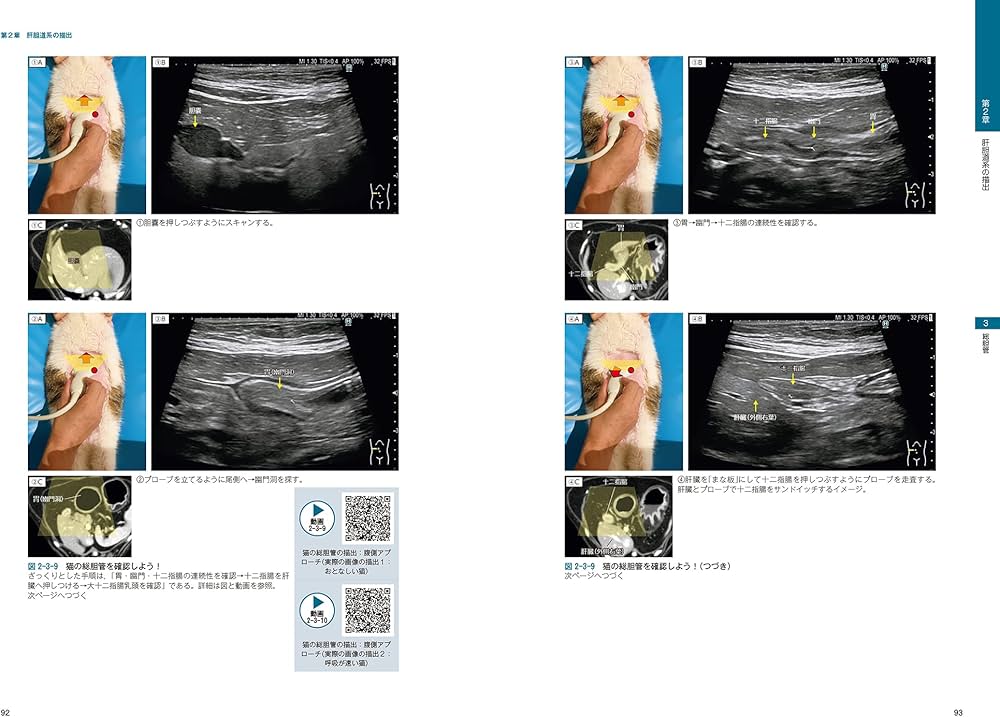

「ビジュアルと動画でわかる! 犬と猫の腹部超音波の描出レッスン 下巻 : 副腎/膀胱・尿道/生殖器/膵臓/消化管」目立った傷や汚れはありませんが傷や汚れありとしています。素人裁断につき、不揃いな面があるかもしれません。神経質な方はご遠慮願います。背表紙はありません。定価+送料で買うより安いです。#獣医#麻酔#犬と猫#犬#猫#小動物